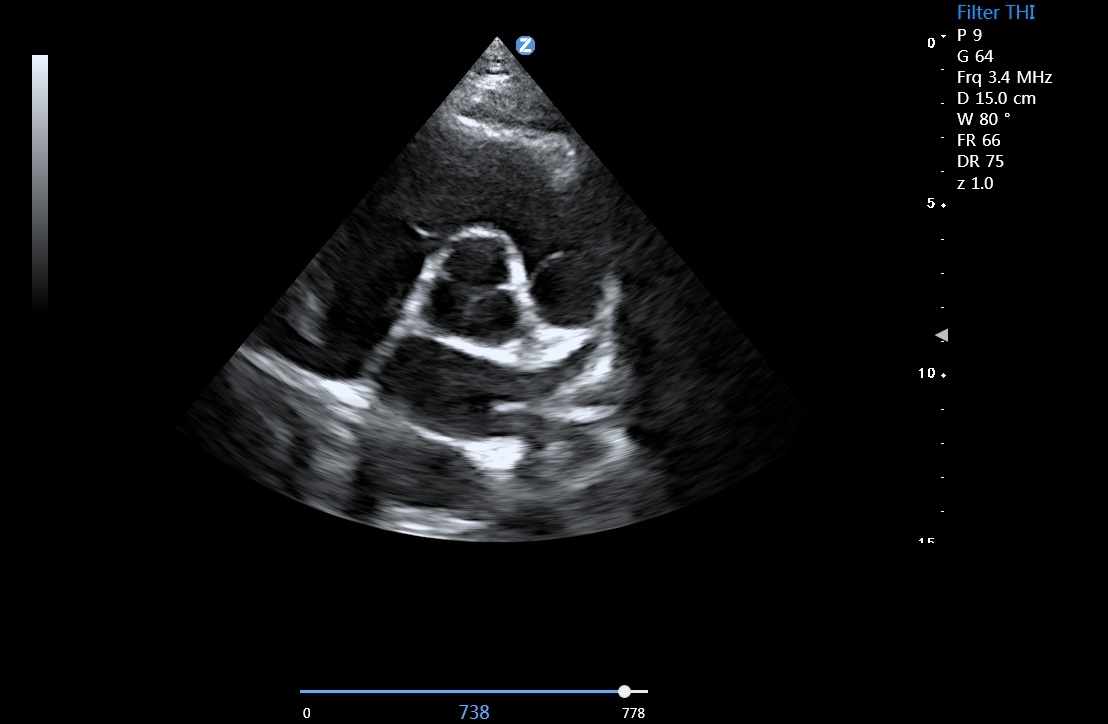

组织多普勒成像

支持TDI组织多普勒成像(TVI、TEI、TVM和TVD)

优异的临床图像